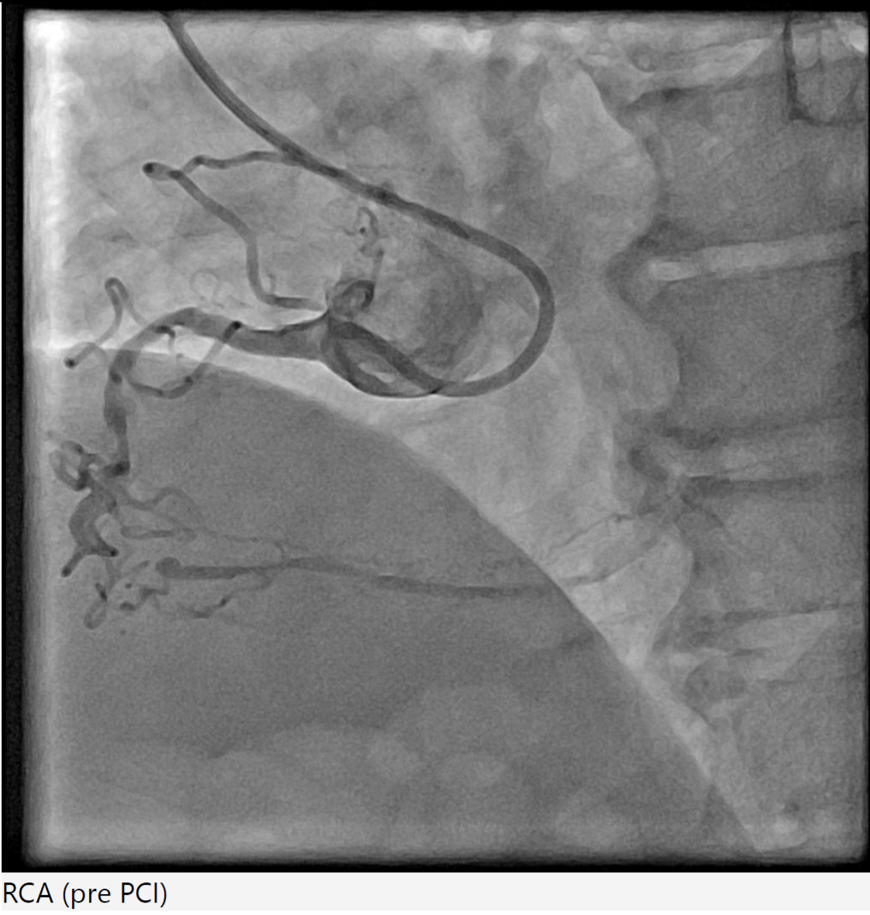

Coronary angiography revealed triple-vessel disease with distal left main involvement, 80% ostial LAD stenosis, 99% ostial LCx stenosis, and a chronic total occlusion of the mid RCA supplied by septal-septal collaterals from the LAD.

Right radial 6Fr JR 4.0 initially for antegrade RCA CTO attempt, subsequent switched to AL 1.0 for better support. CTO lesion crossed using Gaia Next 3 wire with Finecross microcatheter support, pre-dilatation using SC Sapphire 1.0 ¡¿ 8 mm balloon. However, guide catheter induced aorto-ostial dissection (Dunning Class II) occurred during catheter manipulation and contrast injection. The dissection was promptly recognized and proceed strategy of seal the dissection via ping pong technique. Second access via right femoral 6Fr long sheath due to tortuous iliac artery with JR 4.0, Sion Blue wire crossed to distal RCA. The ostial-proximal lesion is predilated with NC Trek 3.5 ¡¿ 12 mm balloon, then stented with Biofreedom 3.5 ¡¿ 24 mm and post dilate with NC Trek 3.5 ¡¿ 12 mm balloon. The mid to distal RCA lesion is prepared using SC Euphora 2.0 x 15 mm balloon with AL 0.75 catheter and Telescope guide extension support. Further predilate with Lacrosse Aperta 3.0 x 13 mm and NC Sapphire 3.0 x 10 mm balloon. Distal RCA treated with DCB Essential Pro 3.0 ¡¿ 40 mm. Proximal to distal RCA stented with Biofreedom 3.5 ¡¿ 24 mm and Biofreedom 3.5 ¡¿ 36 mm (overlapping from ostial to distal). Final post-dilatation with NC Trek 3.75 ¡¿ 8 mm (mid–distal) and NC Sapphire 4.5 ¡¿ 8 mm (proximal). Final IVUS guidance via AL 0.75 guiding catheter and Telescope guide extension showed good result without hemodynamic compromise. Total contrast 240 mL, fluoroscopy 132 mins.

This case highlights a rare but significant complication of catheter-induced RCA aorto-ostial dissection during PCI for chronic total occlusion. RCA CTO lesions pose technical challenges due to heavy calcification, tortuous course, and limited guide support. In this case, deep seating of the guiding catheter during contrast injection likely precipitated an aorto-ostial tear. Timely recognition and immediate sealing with overlapping DES — guided by IVUS — prevented progression into the ascending aorta and avoided emergent surgical conversion.